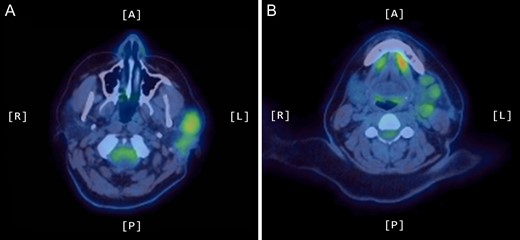

A positron emission tomography (PET) scan was subsequently arranged, which demonstrated increased uptake of the left parotid gland and several enlarged lymph nodes in the neck bilaterally (Figs 1 and 2).

Axial PET scans (A and B) showing increased uptake of the left parotid gland and enlarged left-sided lymph nodes in the neck.